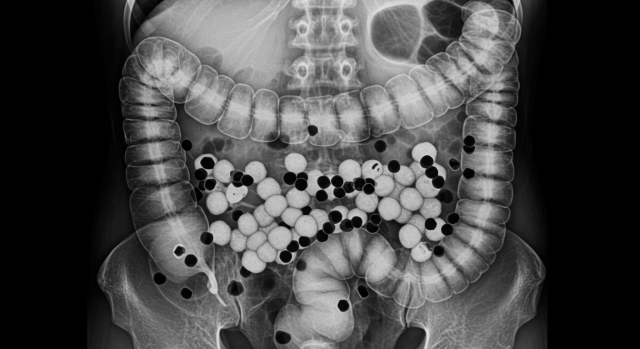

실제 사례는 우리가 왜 버블티를 조심해야 하는지를 분명히 보여줍니다. 대만에서는 물 대신 단 음료와 버블티를 즐겨 마시던 20대 여성이 심한 통증으로 병원에 실려갔습니다. 검사 결과, 그녀의 몸에서 무려 300개가 넘는 콩팥 결석이 발견되었죠. 이는 단순히 우연이 아니라, 과도한 당분·인산염·옥살산염 섭취의 결과였습니다.

또 다른 사례로, 중국의 한 14세 여학생은 버블티 펄이 소화되지 않은 채 장에 남아 심각한 변비를 일으켰습니다. 검사 결과 복부를 막고 있던 펄이 100개 이상 발견되었을 정도였습니다. 이런 사례들은 단순히 ‘살이 찌는 음료’ 수준이 아니라, 생명을 위협할 수 있는 심각한 위험성을 내포하고 있음을 보여줍니다.